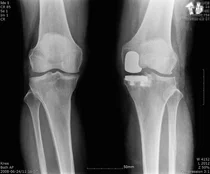

연세사랑병원, ‘PNK 인공관절’ 식약처 허가 획득

연세사랑병원은 후방십자인대를 보존하는 한국형 인공관절 CR타입을 개발, 식품의약품안전처 허가를 받았다고 1일 밝혔다. 현재는 FDA의 승인 절차를 밟고 있어 코렌텍에 이은 국산 인공관절의 성공적인 해외 진출에 대한...

'인공관절' 부담스럽다면 '부분치환' 권장

무릎 퇴행성관절염은 무릎 관절이 노화하고 퇴화하며 염증이 생긴 상태다. 이에 앉을 때, 계단을 오르내릴 때 등 일상생활에서 통증으로 많은 어려움을 초래하게 된다.